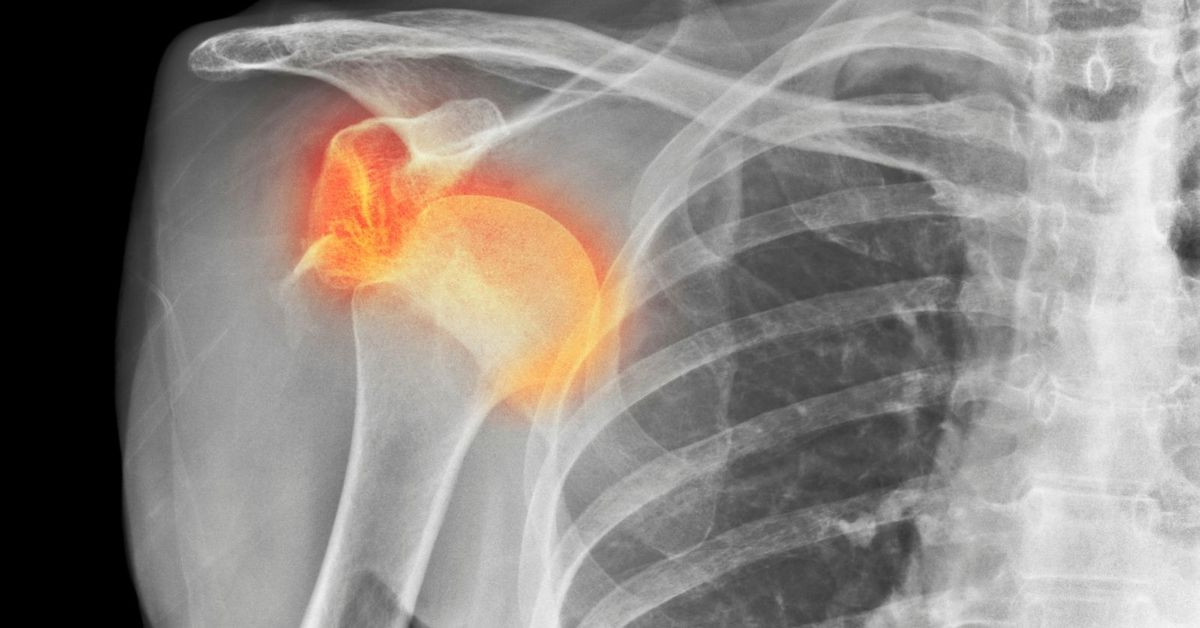

Kol kemiğinin omuz yuvasından çıkmasıdır. Omuz çıkığı, genellikle ani bir darbeyle oluşur. Omuzda şiddetli ağrı görülür. Hareket kısıtlanır. Şişlik ve şekil bozukluğu olabilir. Spor kazaları sık nedendir. Tedavi için kemik yerine oturtulur. Sonrasında fizik tedavi gerekebilir. Erken müdahale önemlidir. Tekrarlama riski vardır. Uygun egzersizle korunmak mümkündür.

Çıkık sırasında omuz eklemi yerinden çıktığı için görsel olarak omuzda belirgin bir deformasyon olabilir. Omuz, normalden farklı bir şekilde görünebilir ya da eklem bölgesinde anormal bir şişlik meydana gelebilir. Çıkık, sinirleri veya damarları sıkıştırabilir, bu da ellerde uyuşma, karıncalanma ve zayıflığa yol açabilir. Kişi, elini ya da parmaklarını hareket ettirmekte zorluk çekebilir. Kaslarda zayıflığa neden olabilir. Bu, özellikle omuz kaslarının gerilmesi ya da hasar görmesi nedeniyle yaşanır. Kişi, kolunu kaldırmada zorluk çekebilir.

Çıkık nedeniyle bir kişi, omuzunu kullanarak herhangi bir şey tutmakta veya taşıma işlemlerinde zorluk yaşayabilir. Ayrıca, kolunu vücuda yaklaştırmak ya da kaldırmak da ağrılı olabilir. Eklemdeki tüm yapıları etkileyebilir ve bazen bıçak saplanıyormuş gibi bir ağrıya yol açabilir. Bu ağrı çoğu zaman aniden başlar ve kişiyi hareketsiz hale getirebilir. Eğer belirti fark edilirse, hemen bir doktora başvurulmalıdır. Omuz çıkığı, genellikle acil müdahale gerektiren bir durumdur.